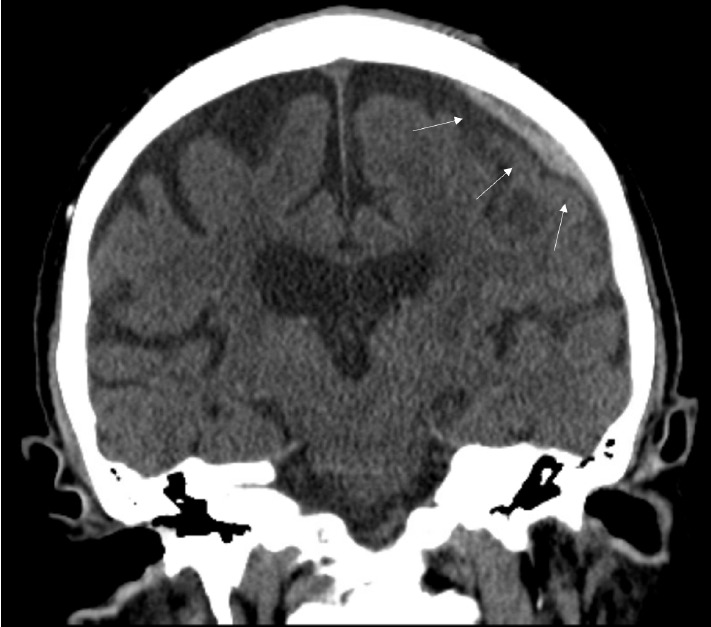

We present a case of a meningo-meningeal arteriovenous fistula (MMAVF) discovered immediately following middle meningeal artery (MMA) microparticle embolization for the treatment of an acute subdural hematoma (SDH). An elderly patient presented with an SDH found during stroke workup. MMA embolization was elected due to his need for therapeutic anticoagulation. During the procedure, multiple MMAVFs appeared after microparticle embolization of the distal MMA branches. We aborted further microparticle embolization and performed coil embolization of the MMA trunk with cessation of flow. No clinical complication was noted postoperatively and no post-procedure hemorrhage was seen. Review of literature suggests that this phenomenon may be associated with microparticle embolization. We hypothesize the cause to be vessel rupture due to barotrauma during manual injection via the microcatheter. As MMA embolization becomes more common, this complication may become more recognized.